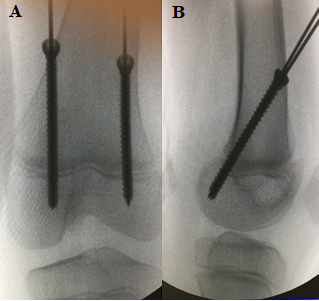

Using images in the coronal and sagittal planes with the fluoroscopy aid, two guide wires were inserted percutaneously (one for each incision), from proximal to distal and anterior to posterior, crossing the femoral distal physis with a 45 degrees angle at its posterior third, close to the subcortical limit of the medial and lateral femoral condyles. Two steel cannulated screws 4.5 mm thick were then inserted using two guide wires (Followmed®), with the screws tips fully located in the distal medial and lateral femoral condyles (Figures 1A & 1B). Then, suture of the subcutaneous tissue and the skin was performed.

Figure 1A,B Intraoperative control of posterior hemiepiphysiodesis of the distal femur, with two cannulated steel screws guided by metallic wires (1A profile view; 1B AP view) for treatment of deformity in recurvatum knee in a 9-year-old patient due to hemiparetic cerebral palsy.